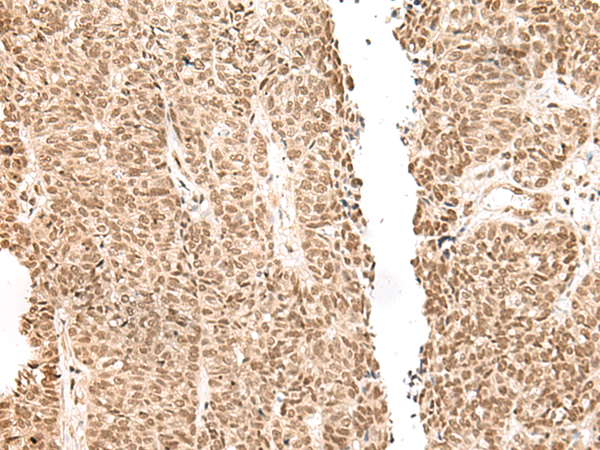

IHC positive control:

Human ovarian cancer and Human thyroid cancer

IHC Recommend dilution:

30-150